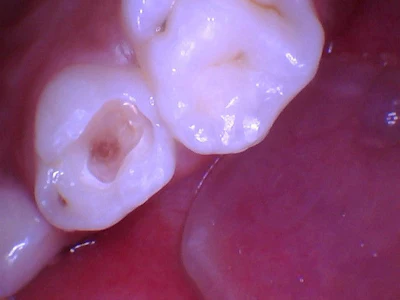

- Preparation: High-speed, green stripe diamond bur and a slow-speed carbide #6 bur, leaving firm dentin (Figure 2)

- Restoration: Glass ionomer liner, total etch, one-step prime and bond, Luna Flow composite resin, and Luna 2 composite resin, shade A2

- Finishing: Football carbide finishing bur and disposable polishing bur

Figure 2: Selective caries removal.

I was impressed with how easy it was to dispense, handle, and sculpt Luna 2 and to see the great aesthetics.